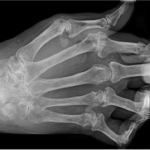

Артриты

Вероятность развития этой воспалительной суставной патологии довольно высока. Реже после простуды диагностируется реактивный артрит. Он возникает или во время простуды, или спустя несколько дней после выздоровления. Толчком к развитию заболевания становится проникновение в организм инфекционных агентов. Вирусы и бактерии необязательно попадают в суставную полость. Реактивный артрит возникают у людей, предрасположенных к нему из-за гиперреакции иммунной системы. Она обнаруживает циркулирующие в кровеносном русле чужеродные белки и начинает продуцировать антитела для их уничтожения. Но на определенном этапе происходит сбой — иммунная система атакует клетки сустава, провоцируя развитие воспалительного процесса.

После перенесенных вирусных или бактериальных респираторных инфекций возникают и другие виды артрита:

- инфекционный. Патогенные микроорганизмы проникают в полость сустава из первичных воспалительных очагов. Они выделяют в процессе жизнедеятельности токсичные вещества, повреждающие ткани. Это становится причиной воспаления, в том числе сопровождающегося накоплением гнойного экссудата;

- ревматоидный. Этиология и патогенез этого вида артрита до конца не изучены. Обнаружена взаимосвязь нарушения иммунного ответа на проникновения определенных типов вируса, обычно герпесвирусов. Воспаляется синовиальная мембрана (синовит), формируются грануляционные ткани. Они постепенно разрастаются, проникают в гиалиновые хрящи, разрушая их.

Только ревматоидный артрит относится к пока неизлечимым заболеваниям. Остальные виды патологии хорошо поддаются терапии, но только при своевременном ее проведении. Для диагностирования артритов применяются как инструментальные, так и биохимические методики. При внешнем осмотре ревматолог обращает внимание на отечность сустава, покраснение кожи, тугоподвижность. Для лечения назначают такие местные и системные средства: